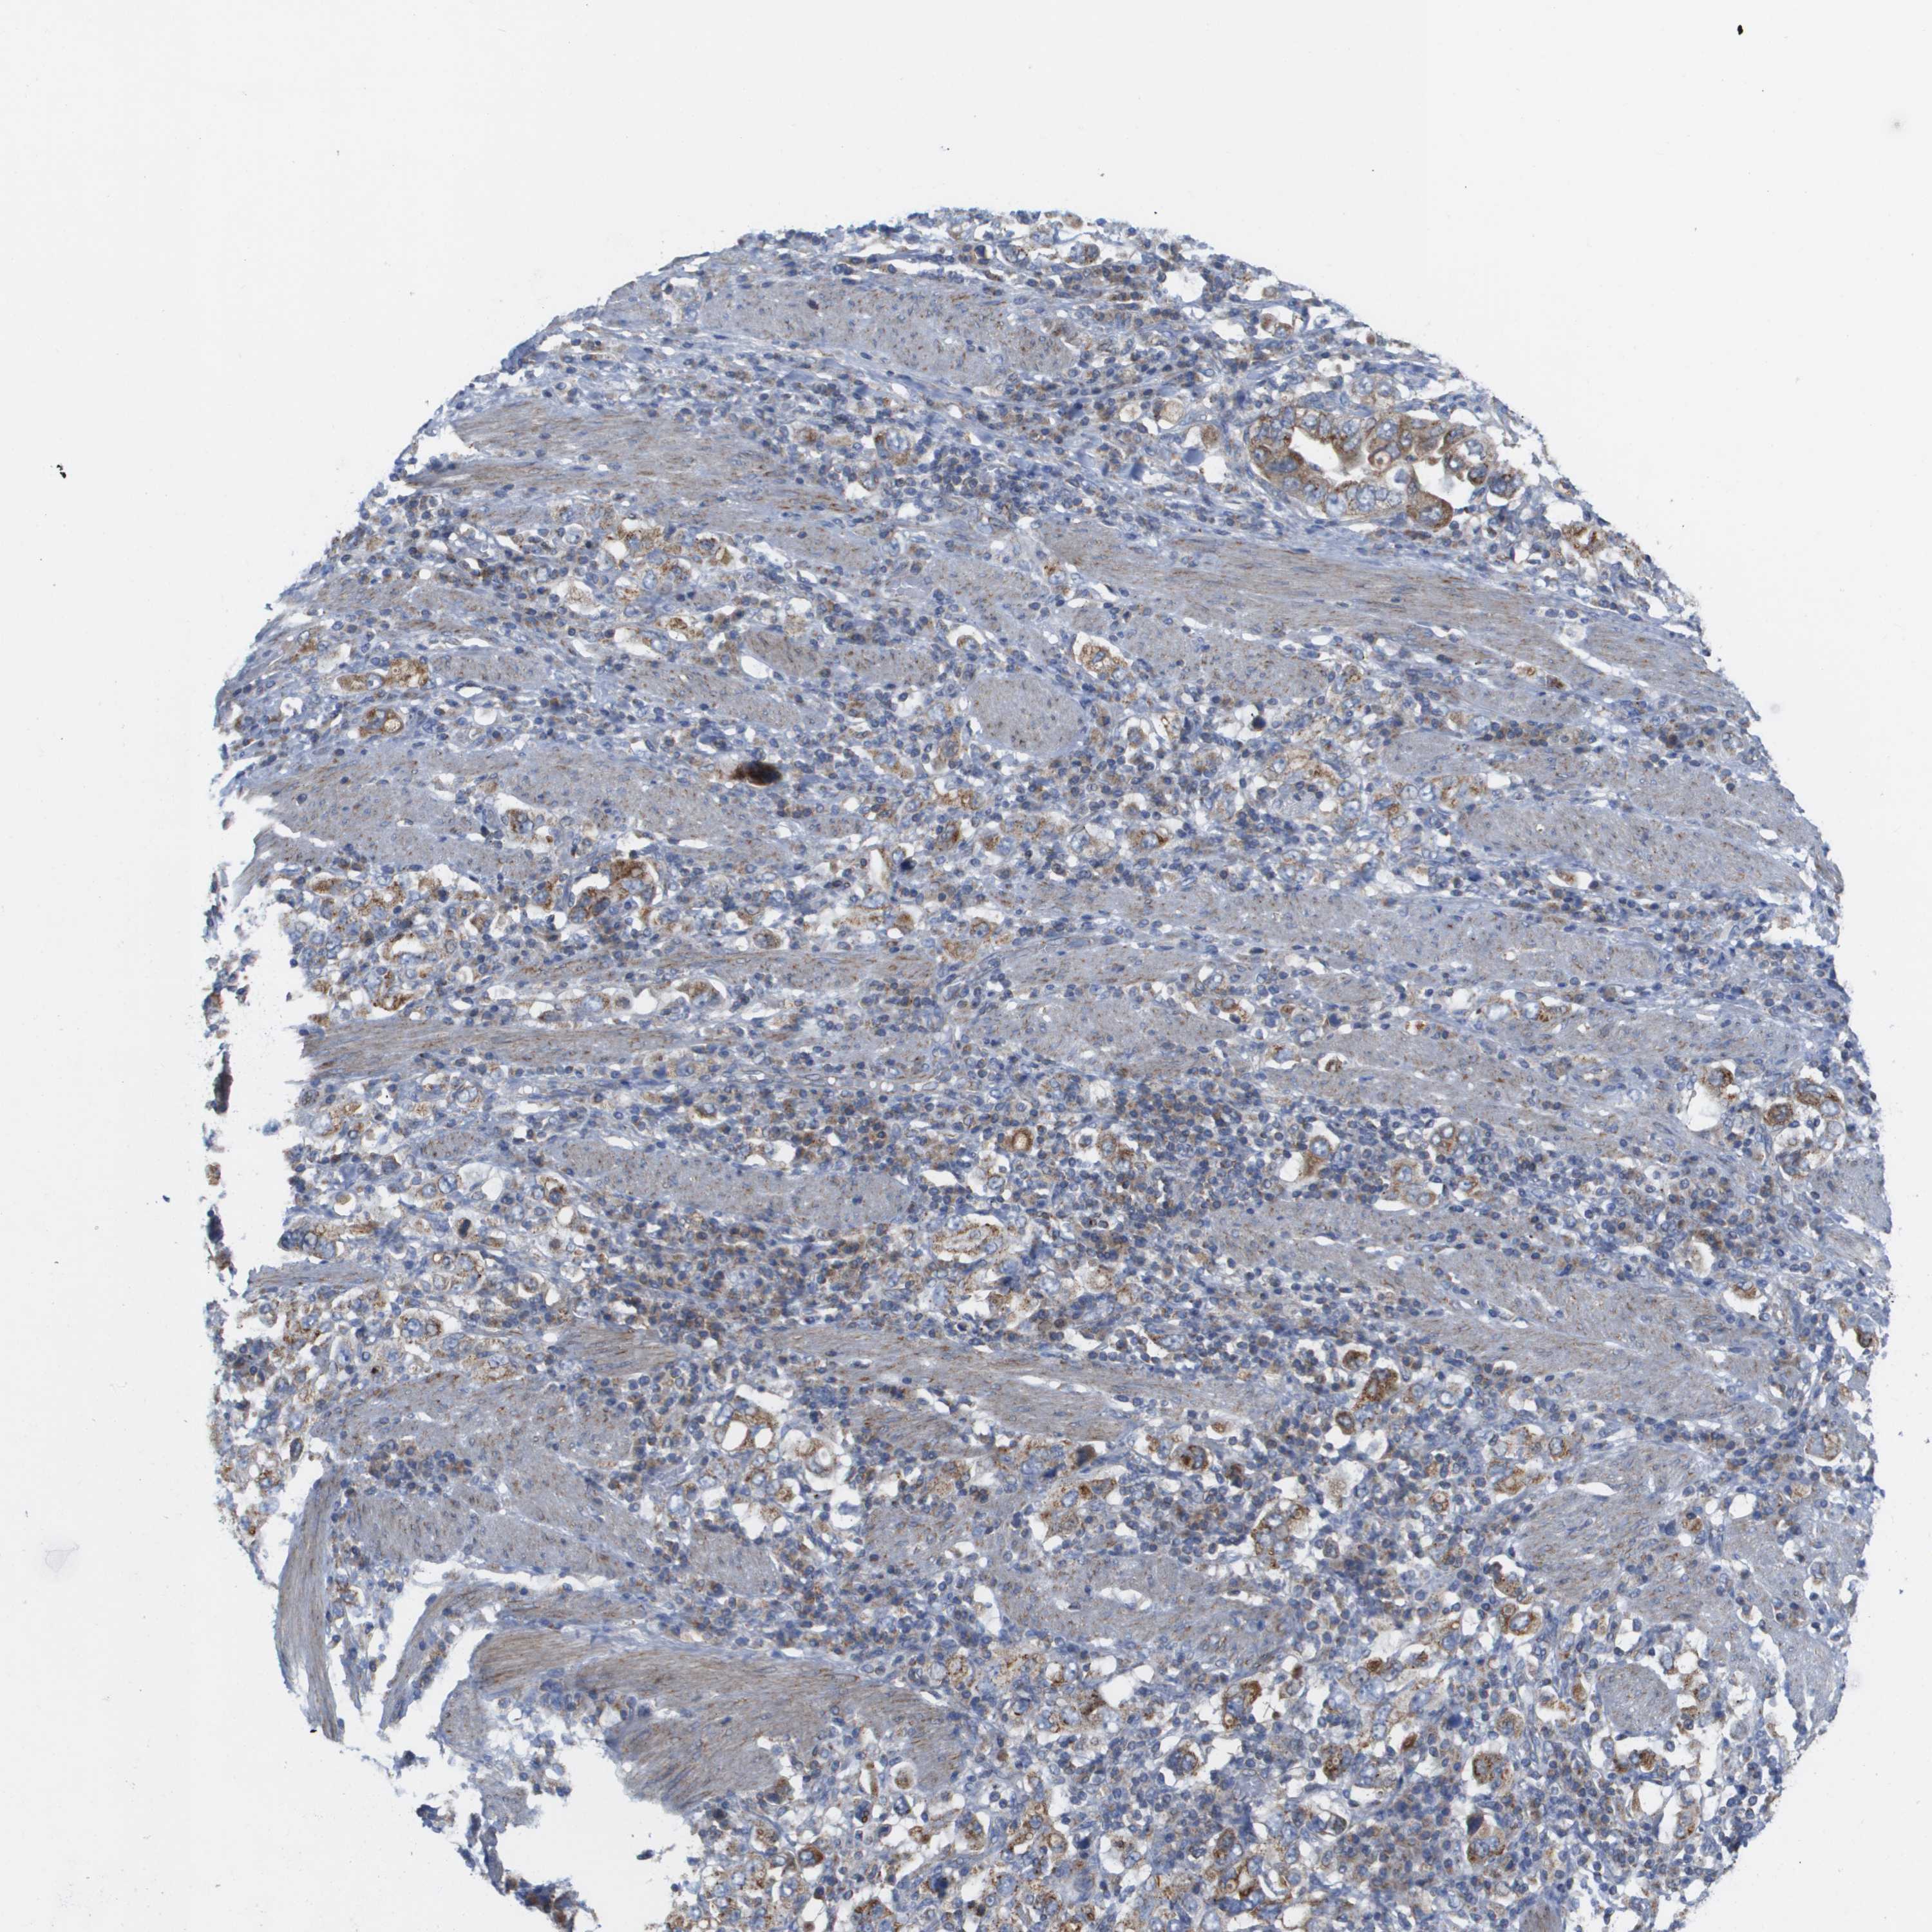

STOMACH CANCER - Protein expressioni

A mouse-over function shows sample information and annotation data. Click on an image to view it in a full screen mode. Samples can be filtered based on level of antibody staining by selecting one or several of the following categories: high, medium, low and not detected. The assay and annotation is described here.

Antibody stainingi

Antibody staining in the annotated cell types in the current human tissue is reported as not detected, low, medium, or high, based on conventional immunohistochemistry profiling in selected tissues. This score is based on the combination of the staining intensity and fraction of stained cells.

Each image is clickable and will lead to virtual microscopy that enables deeper exploration of all samples and also displays staining intensity scores, fraction scores and subcellular localization as well as patient and tissue information for each sample.

Antibody HPA017430

Staining

High

Medium

Low

Not detected

Intensity

Strong

Moderate

Weak

Negative

Quantity

>75%

75%-25%

<25%

None

Location

Nuclear

Cytoplasmic/membranous

Cytoplasmic/membranous,nuclear

Adenocarcinoma, NOS